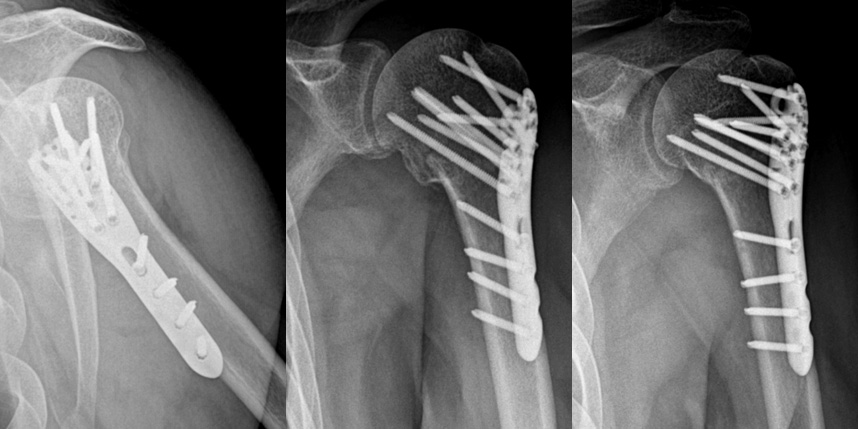

상완골 골절

골절이 심하지 않은 경우에는 깁스로 고정해서 유합을 시킬 수 있으나, 정도가 심한 경우에는 손,발목 골절 수술을 진행할 수 있습니다.

골절은 정확하게 골절편을 잘 맞추고 고정하는 것이 중요합니다. 특히 관절면을 잘 맞추는 것이 중요합니다.